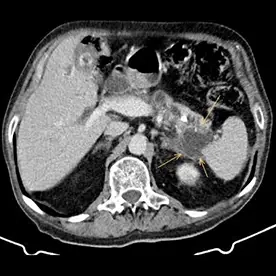

Durchführung einer kontrastmittelgestützten CT-Untersuchung des Abdomens in arterieller und venöser Kontrastmittelphase. Neben einer reizlosen Cholezystholithiasis zeigt sich ein massiv erweiterter D. pancreaticus bis zur Papille und diffuse zystische Pankreasläsionen, teils mit Verkalkungen (Bild 4 und 5) mit dem Hauptbefund im Pankreasschwanz angrenzend an die linke Nebenniere; kein Nachweis solider Anteile (Bild 1). Zusätzlich wurden mehrere kalkdichte Konkremente im Pankreas nachgewiesen, die sich vorwiegend im Bereich des Caput befinden. Keine Lymphadenopathie. Keine metastasensuspekten Herdsetzungen. Als weitere Nebenbefunde wurden eine parenchymverschmälerte Niere rechts und der V.a. auf ein Nebennierenadenom geäußert.

Verdacht auf eine intrapankreatische muzinöse Neoplasie (IPMN) vom Hauptgangtyp. Auch die intra- und extrahepatischen Gallenwege zeigen sich deutlich dilatiert (Bild 2 und 3).